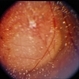

Choroidal Melanoma With Vitreous Seeding

Choroidal Melanoma

Underlying retinal choroidal melanoma with dense vitreous seeding of choroidal melanoma cells.